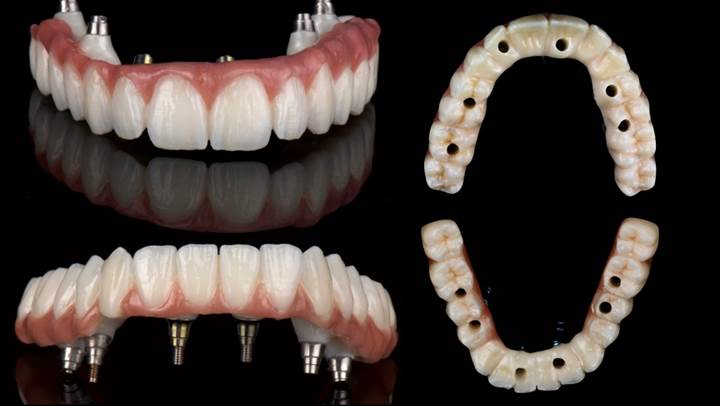

Clinical case: AFull transition from natural teeth to all-on-6 bridges

with AnyRidge implants

- Courtesy of Dr. Rabih Abi Nader, UAE -

Full-mouth rehabilitation, minimal layering, Zirconia, all-on-6, life changing result, edentulous ,Dr. Rabih Abi Nader, AnyRidge

AnyRidge implant system